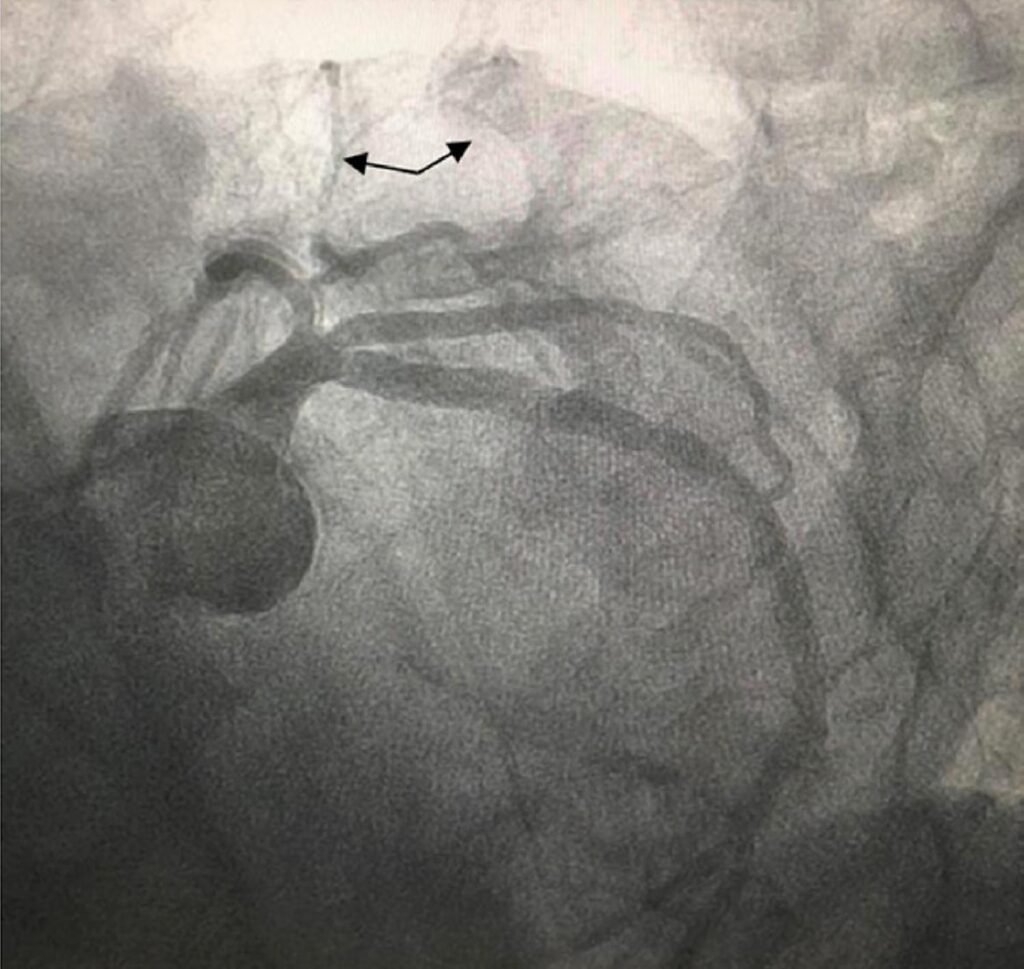

Coronary–Cavitary Fistula of the Circumflex Coronary Artery to the Left Atrium as a Probable Etiology of Heart Failure: A Case Report

Coronary artery fistulas have a low incidence and are often diagnosed by echocardiography or coronary computed tomography angiography, although coronary angiography is the gold standard. They commonly originate in the right coronary artery, with drainage to low-pressure chambers being the most frequent finding. Treatment can be expectant, surgical, or percutaneous. This report describes a case of a rare presentation of heart failure due to a fistula of the circumflex coronary artery with drainage into the left atrium.